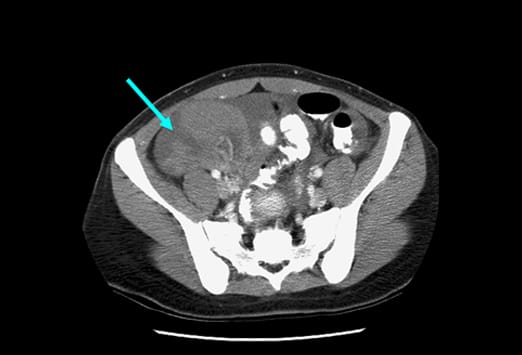

Diese Abbildung zeigt einen Appendikolithen (weißer Pfeil) mit einem großen Abszess (blau gestrichelte Linie), der einzelne Lufteinschlüsse enthält (roter Pfeil). Es zeigen sich angrenzend weitere entzündliche Veränderungen im Bereich des terminalen Ileums (gelber Pfeil). Eine Perforation stellt die schwerste Form der fortgeschrittenen Appendizitis dar, da es hier zu einer Infektion der Bauchhöhle kommt. Eine Perforation kann somit einen Abszess, eine Peritonitis und einer Sepsis zu Folge haben.